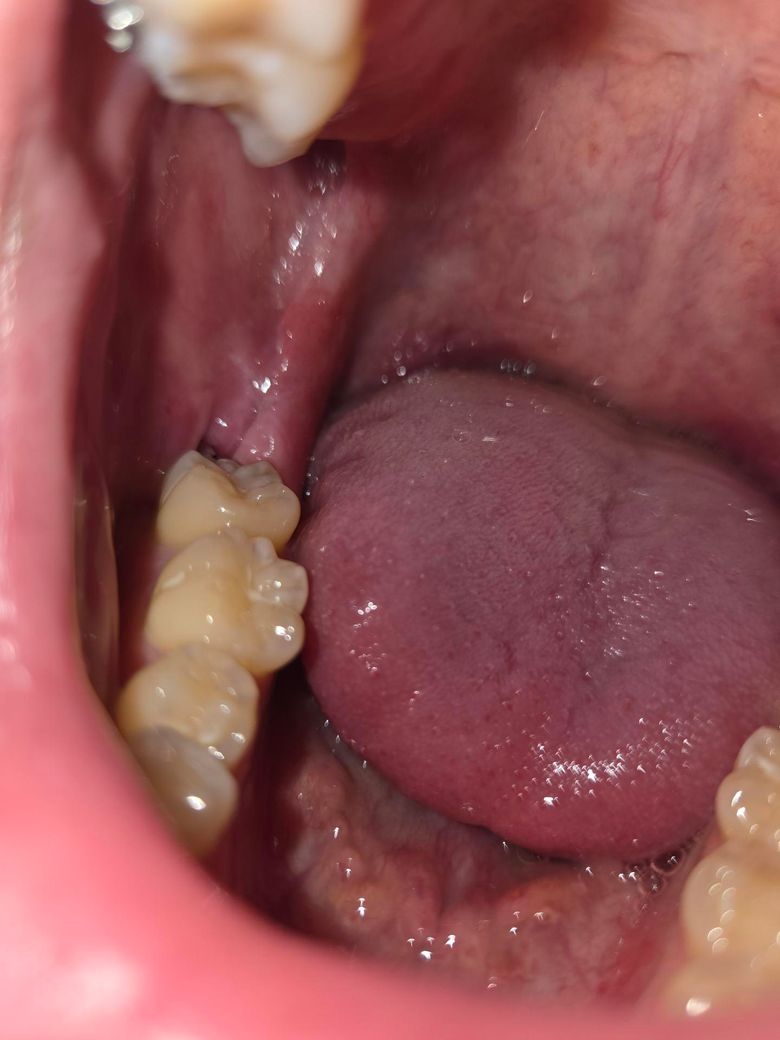

사진상으로 오른쪽에 발치 부위가 있는게 2주 전에 사랑니 발치한 곳이고, 왼쪽에 있는게 1주 전에 발치한 곳입니다. 그런데 2주 전에 발치한 곳은 구멍이 커보이고, 1주 전에 발치한 곳은 구멍이 작아보여서 혹시 이상있는 것인지 궁금해 질문드립니다. (통증은 없습니다. 워터픽 가장 약한 수압으로 하는데도 통증은 없습니다.)

• 2번 째 사진